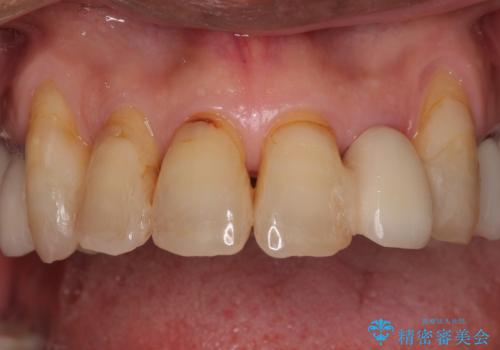

ただし、長期間欠損を放置していたことで、咬み合う上の奥歯が動いてしまっていたので、まずは上顎奥歯の部分矯正を行い、より理想的な咬み合わせを目指すこととしました。

部分矯正を行ったことで、違和感のない咬み合わせを達成することができました。